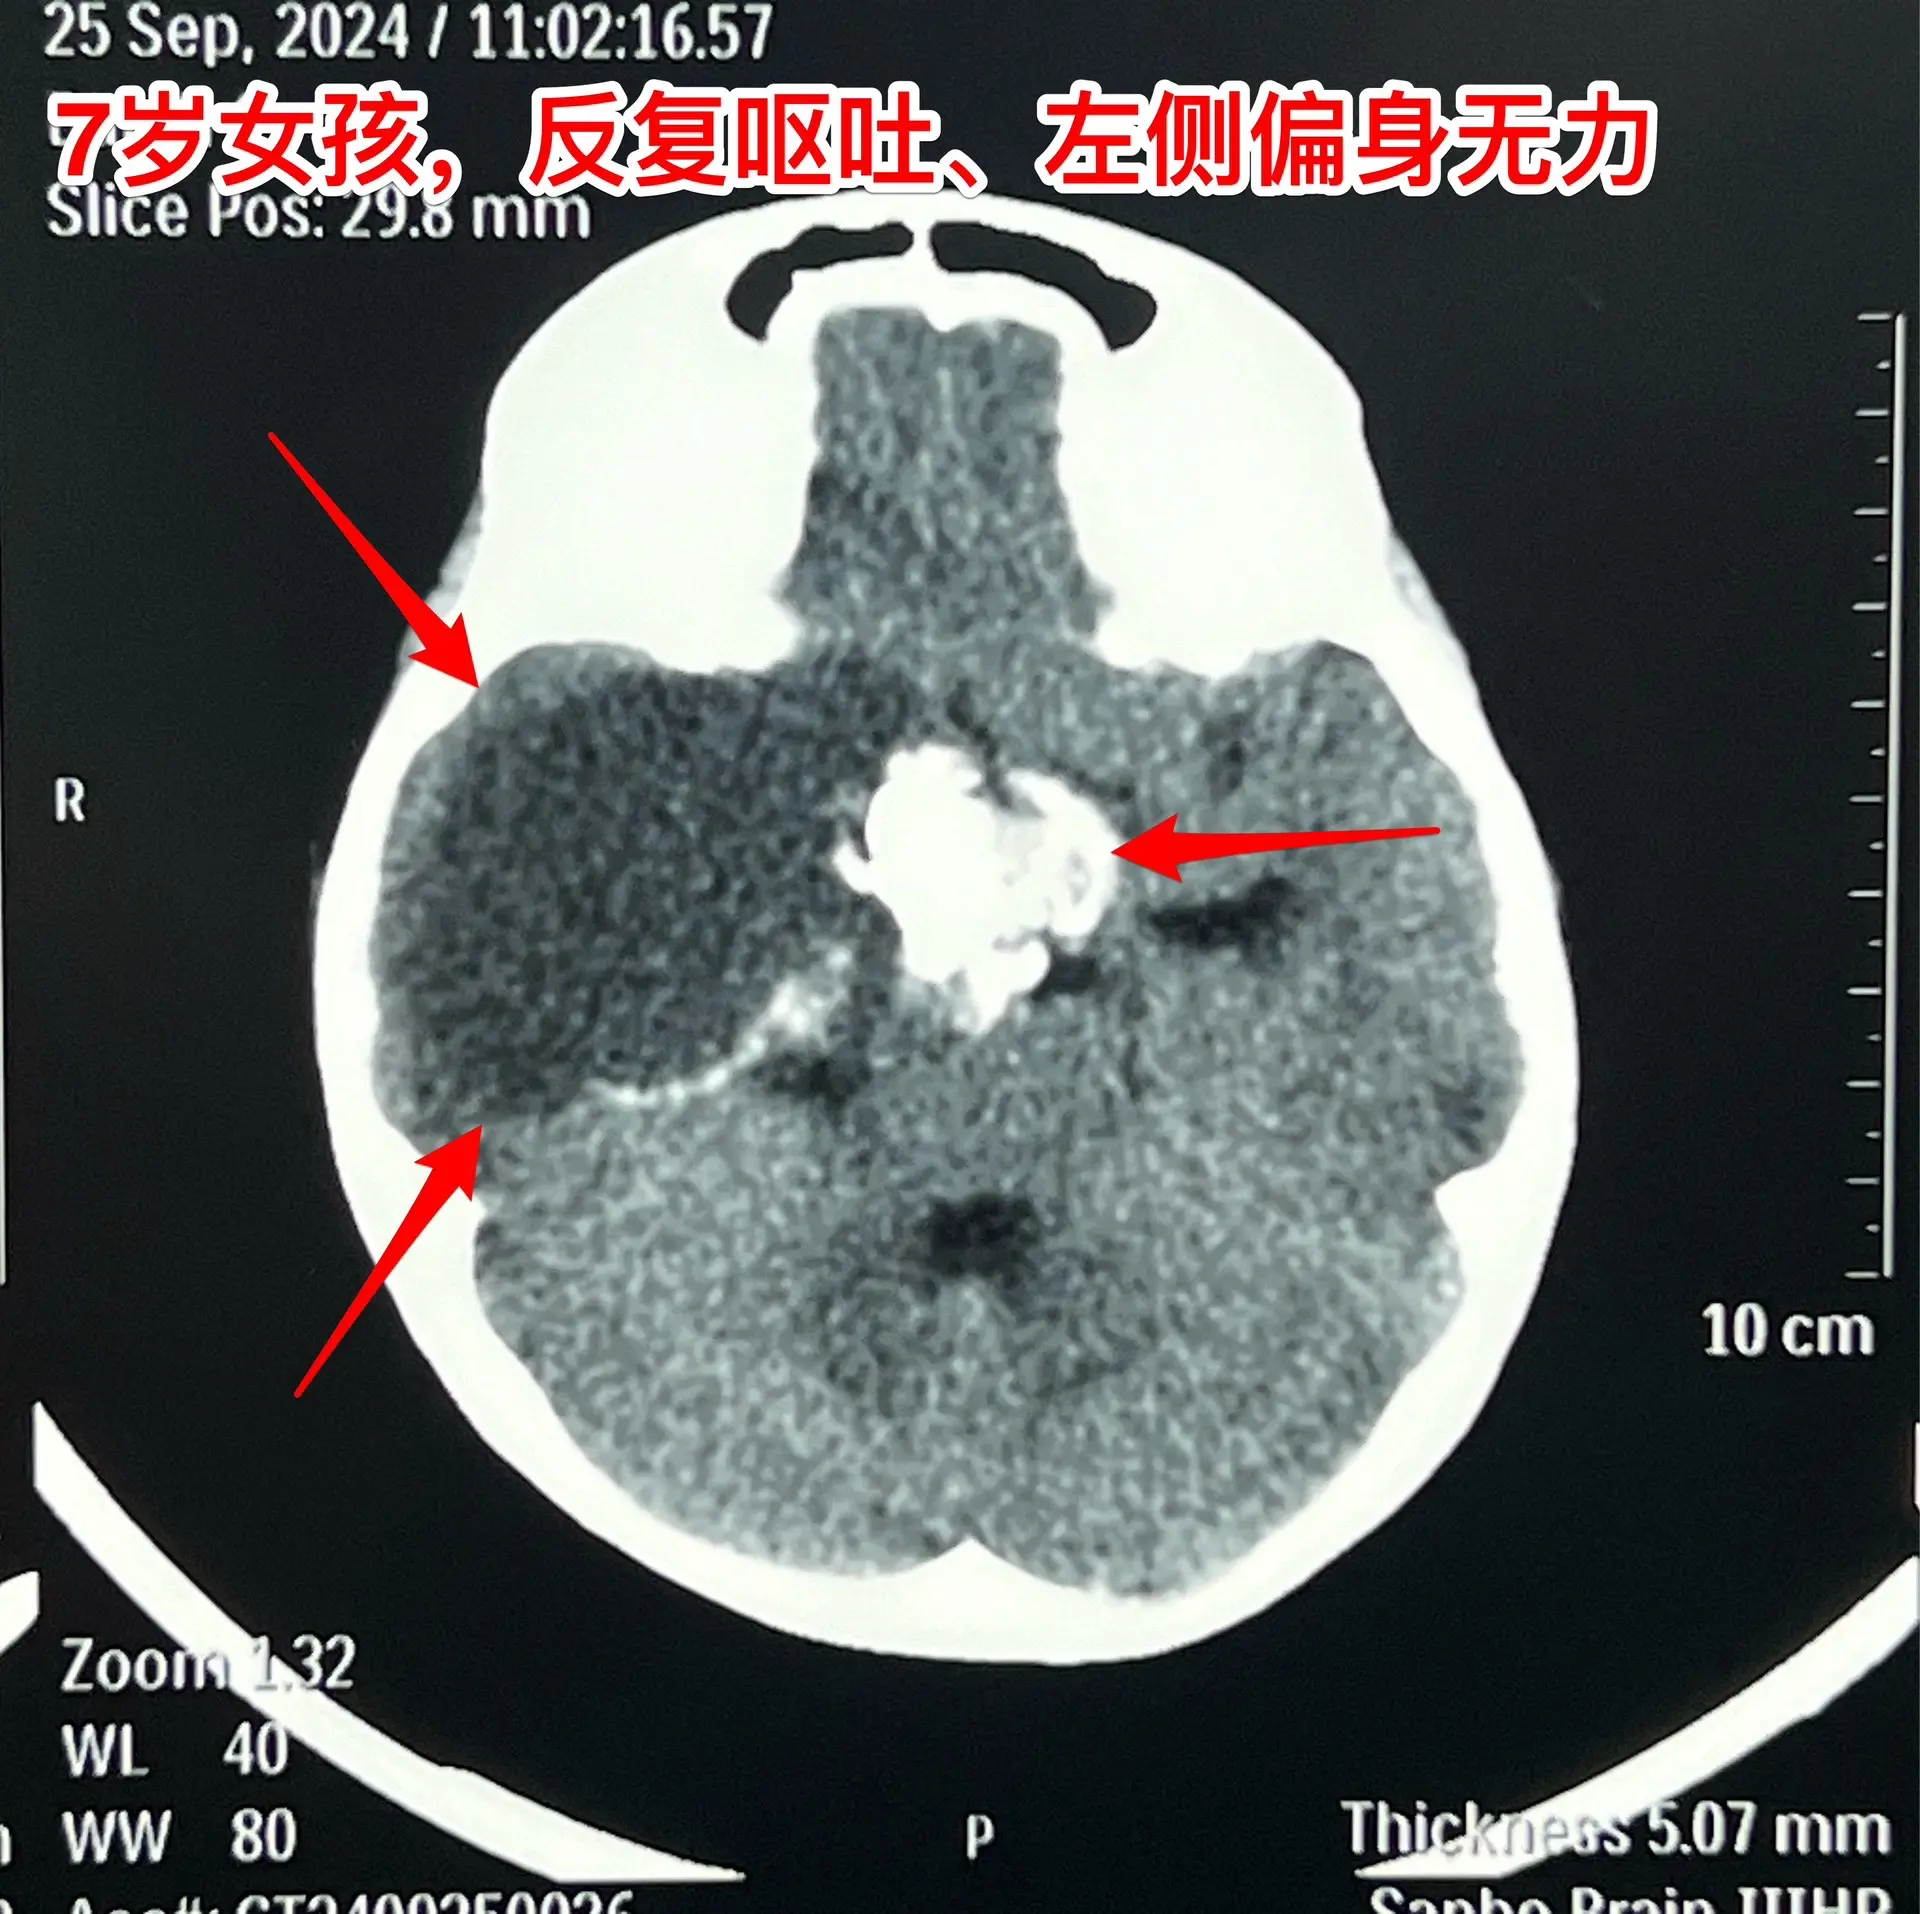

漳州市女孩子脑部长了巨大的颅咽管瘤。7岁漳州市女孩子,入院前两个月经常出现呕吐,按胃肠疾病治疗无效。入院前20天出现左侧上下肢活动力弱,伴有左上肢抖动。在厦门某医院经CT检查发现是脑部肿瘤。 从头CT可以看出这是典型的颅咽管瘤,鞍区有很大的钙化团块,小块肿瘤侵入第三脑室,肿瘤囊向右侧颞部及基底节区生长并有推挤压迫效应。手术有难度啊! 我们的手术入路设计思路:肿瘤起源点在中线,有大块钙化,是手术的难点,故以中线方向为主攻方向,争取将肿瘤的起源点及钙化完全切除!而向右侧颞部生长的肿瘤囊虽然体积大,只是肿瘤的扩张产物,切除的难度并不大,故右侧裂方向只需迂回攻击即可搞定。按这个思路设计手术方案后,手术中也有出乎意料的环节。鞍上的肿瘤钙化块又大又硬,花费很大精力才能将其体积减小,从视交叉前间隙取出。肿瘤囊从颈内动脉下方侵入颞叶,一部分囊自颞部向中线方向返折嵌入到基底节区。如术前所料,这部分囊性肿瘤切除难度不是太大。肿瘤最终得到完全切除,手术后患儿精神好,四肢活动自如。